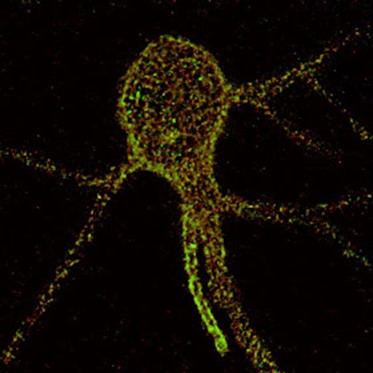

صورة لخلية بارفالبومين parvalbuminالعصبية البينية تبين شبكات الخلايا العصبية المحيطة «باللون الأحمر» تتكون من بروتين أغريكان «باللون الأخضر». يمكنك أن ترى بوضوح البنية الشبيهة بالشبكة التي تتكثف حول جسم الخلية والتغصنات العصبونية dendrites القريبة لمركز خلية بارفالبومين العصبية البينية في موقع P60 في القشرة المخية. بإحاطة المشابك العصبية الواردة على جسم الخلية والتغصنات العصبونية، تعمل شبكات الخلايا العصبية المحيطة على استقرار وتقوية الروابط المشبكية.